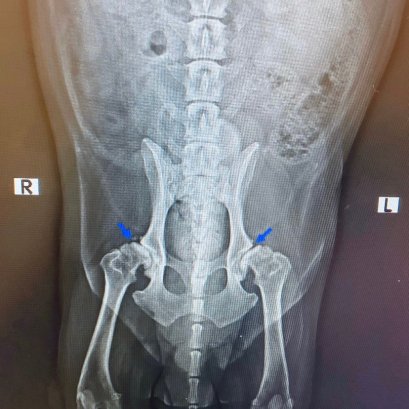

เป็นโรคที่พบได้บ่อย โดยเฉพาะสุนัขพันธุ์ใหญ่ เช่น โกลเด้น รีทรีฟเวอร์ ลาบาดอร์ ร็อตไวเลอร์ เป็นต้น ส่วนสุนัขพันธ์ุเล็กก็สามารถพบได้ โดยโรคนี้จะทำให้สุนัขมีความเจ็บปวด และมีความผิดปกติเวลาเคลื่อนไหวขาหลัง เกิดจากการเจริญของกระดูกข้อสะโพกผิดปกติ ทำให้กระดูกต้นขาไม่สามารถสวมเข้ากับเบ้าสะโพกได้พอดี นำไปสู่การอักเสบเรื้อรัง